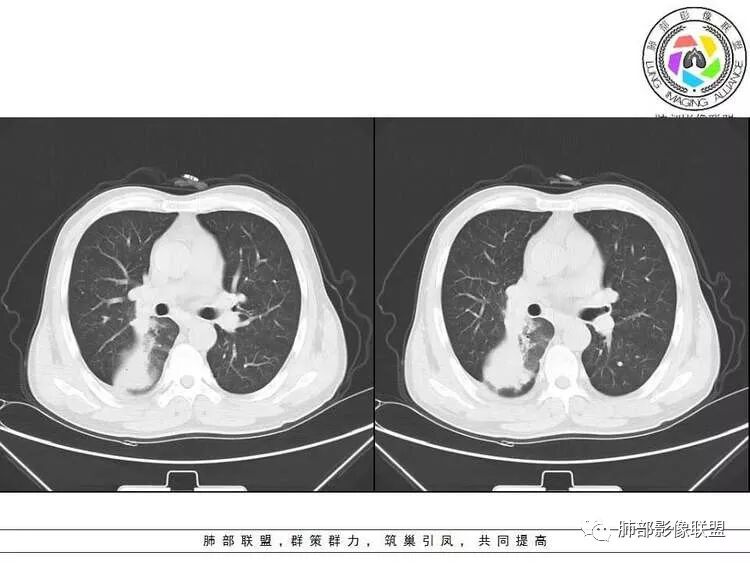

南边:紧贴着斜裂过来的一个病灶,它的特点是:外围大,内带小。它整个下叶背段体积与对侧相比稍微缩小一点,但是缩小地不是很厉害。外支朝前下走了,仔细看血管,肺动脉走行自然,直达远端。远端实变区是肉芽肿成分,稍微有一点低密度,没有明显坏死,稍微有一点点坏死。而且附近有很多卫星灶,附近很多斑片影,有一些明显有气道壁增厚,细支气管炎的特点,还有就是下叶其他段很多斑片状影。换个角度,第一如果是肺癌,刚才看到PET-CT提示肺癌伴阻塞性肺炎,这个是不符合的。第二如果是肺癌阻塞性肺炎,近端血管肺动脉走行不会那么自然集聚的,这个是不符合的。理由是:如果这个病灶是肺癌,那么明显属于中央型肺癌,中央型肺癌的特点是近端大,远端小,近端是一个肿块,远端阻塞,远端阻塞是阻塞性炎症或者不张,它应该体积缩小,斑片状实变,不会这么密实。刚才有老师提到支气管,这个片有缺陷的地方,给的图像好像那层,如果把其他图像拿开再重叠一下。

如果是单纯看这幅图像,会觉得背段外侧支气管分支堵塞的,但是看下面这层图

南边:你就发现外侧支气管朝下走的分支非常自然,通畅的。

右肺下叶背断肿块,外围大,内带相对狭长         远端有膨隆,边缘模糊、凹凸不平         血管走形自然,病灶近端支气管通畅,沿支气管树蔓延         周边有多发病灶,多为磨玻璃密度且边界不清。